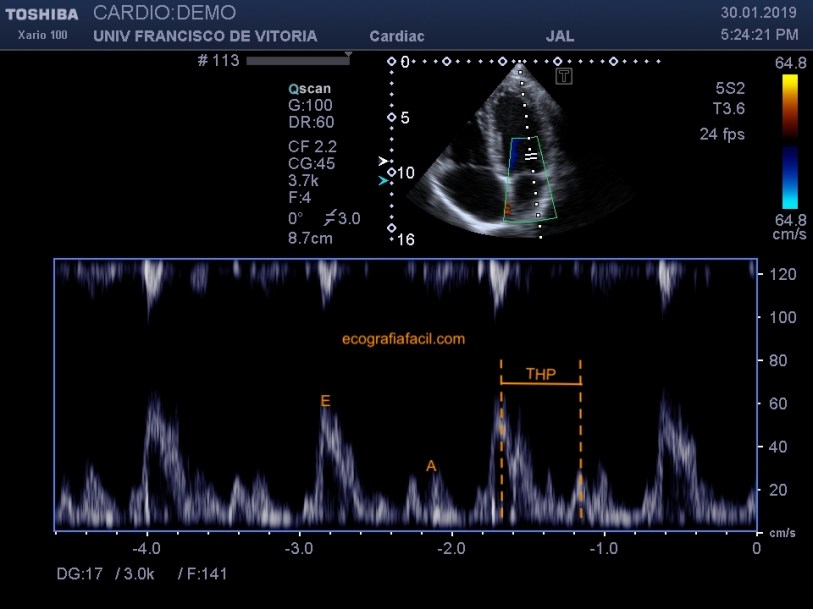

A continuación, pondremos un volumen de muestra a nivel del final de los velos mitrales en el momento de su apertura total para obtener un Doppler espectral que nos permita medir la velocidad de llenado transmitral y el tiempo de hemipresión, parámetros que nos ayudarán a valorar el tipo de ritmo cardiaco (sinusal, fibrilación auricular, alteración de la relajación…) y el área de la válvula (figura 18). Si la velocidad máxima supera 1.5 m/s sugiere que hay estenosis y entonces el Doppler espectral deberá ser contínuo y no pulsado. También usaremos el continuo en casos de prótesis valvular.

Next, we will put a sample volume at the end of the mitral leaflets at the moment of its total opening to obtain a spectral Doppler that allows us to measure the transmitral filling speed and the hemipression time, parameters that will help us to evaluate the type of heart rate (sinus, atrial fibrillation, relaxation disturbance …) and the area of the valve (figure 18). If the maximum velocity exceeds 1.5 m / s, it suggests that there is stenosis and then the spectral Doppler should be continuous and not pulsed. We will also use the continuum in cases of valvular prostheses.